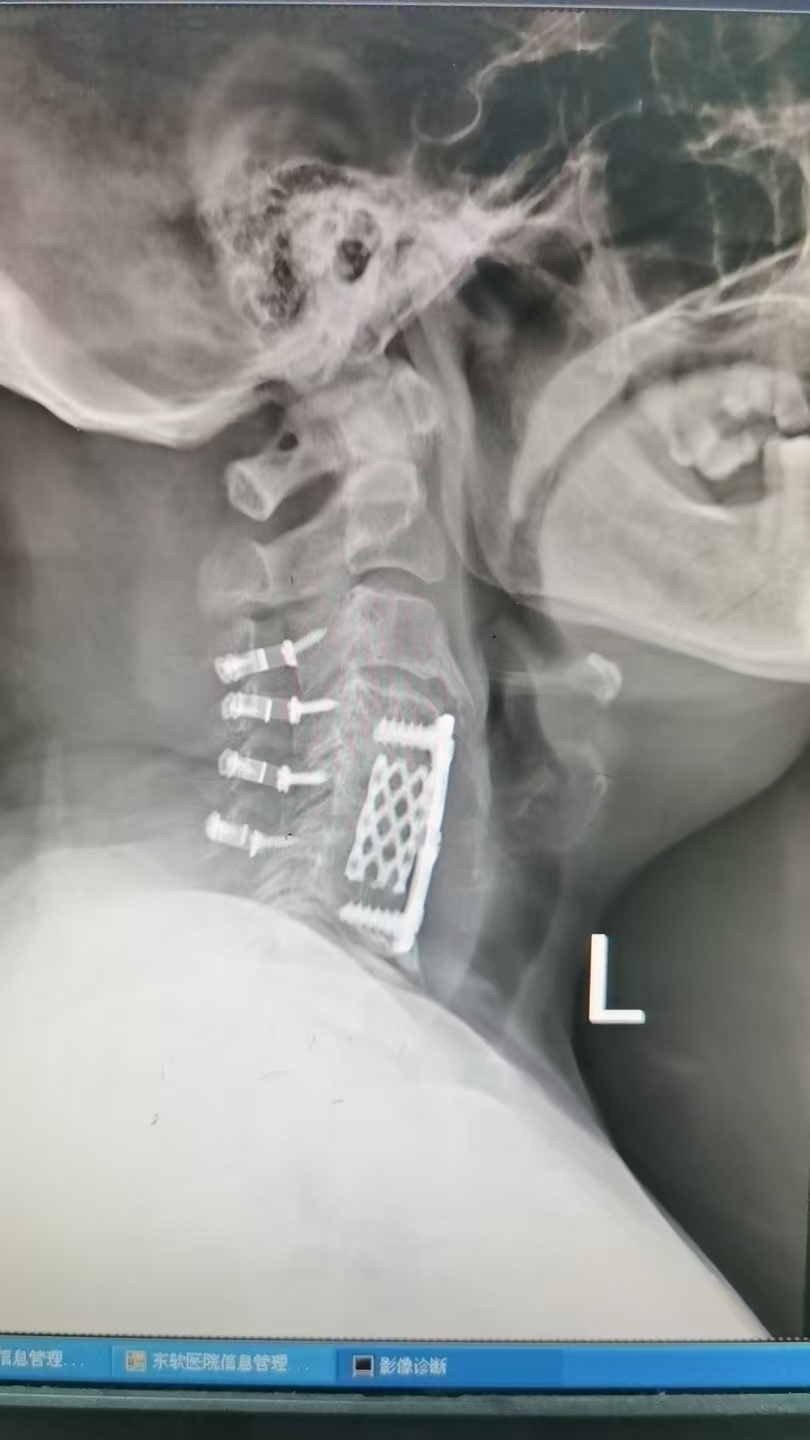

當(dāng)頸椎手術(shù)的“第一次選擇”不再奏效怎么辦?這是一位兩年前因頸椎間盤突出接受了頸椎前路減壓融合術(shù)(ACDF)患者,術(shù)后初期癥狀明顯緩解。然而,從半年前開始,她的雙手逐漸麻木無力,甚至出現(xiàn)行走不穩(wěn)的情況。復(fù)查顯示,原手術(shù)節(jié)段的相鄰椎體出現(xiàn)退變,脊髓壓迫再度加重。最終,廣安門醫(yī)院保定分院的醫(yī)生建議她接受頸椎后路單開門椎管擴(kuò)大成形術(shù)。這種從“前路”轉(zhuǎn)向“后路”的翻修手術(shù),究竟隱藏著哪些醫(yī)學(xué)智慧?為何有些患者需要二次手術(shù)?本文將揭開這一復(fù)雜抉擇背后的真相。前路手術(shù)為何會(huì)“失效”?——認(rèn)識(shí)頸椎手術(shù)的局限性頸椎前路手術(shù)(ACDF)通過頸部前方切口直接切除壓迫脊髓的椎間盤或骨贅,并植入融合器固定,是治療單節(jié)段頸椎病的經(jīng)典術(shù)式。但臨床數(shù)據(jù)顯示,約5%-10%的患者可能在術(shù)后出現(xiàn)癥狀復(fù)發(fā)或加重,常見原因包括:1.鄰近節(jié)段退變:融合后的頸椎力學(xué)改變,導(dǎo)致相鄰椎間盤負(fù)荷增加,加速退化;2.骨融合失敗:植入的椎間融合器未與骨骼完全結(jié)合,出現(xiàn)假關(guān)節(jié)形成;3.新發(fā)病灶:如后縱韌帶骨化(OPLL)進(jìn)展,或椎管狹窄范圍擴(kuò)大;4.脊髓慢性損傷:術(shù)前脊髓已長期受壓,術(shù)后神經(jīng)功能難以逆轉(zhuǎn)。本案例正是因多節(jié)段椎管狹窄合并后縱韌帶骨化,前路手術(shù)無法徹底減壓,最終需后路手術(shù)補(bǔ)救。后路單開門手術(shù):為脊髓“打開一扇窗”后路單開門椎管擴(kuò)大成形術(shù)的原理,是通過頸椎后方入路,將一側(cè)椎板作為“門軸”,另一側(cè)切開后向外掀開,擴(kuò)大椎管容積,解除脊髓壓迫,同時(shí)保留頸椎穩(wěn)定性。其核心優(yōu)勢在于:-廣泛減壓:可同時(shí)處理3-6個(gè)節(jié)段的狹窄問題,尤其適合多節(jié)段病變或OPLL患者;-保護(hù)頸椎活動(dòng)度:相比傳統(tǒng)椎板切除,單開門術(shù)能減少術(shù)后頸椎僵硬;-降低再手術(shù)風(fēng)險(xiǎn):通過鈦板固定“開門”的椎板,長期穩(wěn)定性更佳。手術(shù)關(guān)鍵步驟:1.全麻后取俯臥位,頸部后正中切口;2.剝離肌肉暴露椎板,在一側(cè)椎板與側(cè)塊交界處制作“門軸”(保留內(nèi)層骨皮質(zhì));3.對(duì)側(cè)椎板完全切斷,向外掀開約10-15毫米,擴(kuò)大椎管;4.微型鈦板固定掀開的椎板,留置引流管后縫合。翻修手術(shù)的抉擇:哪些信號(hào)提示你需要二次干預(yù)?頸椎術(shù)后癥狀復(fù)發(fā)≠手術(shù)失敗!但若出現(xiàn)以下情況,需警惕脊髓功能惡化風(fēng)險(xiǎn):-進(jìn)行性肢體麻木無力,尤其是出現(xiàn)“踩棉花感”;-大小便功能障礙或性功能減退;-影像學(xué)顯示脊髓信號(hào)異常(T2加權(quán)像高信號(hào));-椎管狹窄面積>60%或脊髓受壓變形明顯。注意:翻修手術(shù)時(shí)機(jī)需嚴(yán)格評(píng)估。過早手術(shù)可能誤判病情進(jìn)展,過晚則可能錯(cuò)過神經(jīng)修復(fù)窗口期(通常建議在癥狀加重3-6個(gè)月內(nèi)決策)。術(shù)后康復(fù):三個(gè)“黃金階段”決定最終療效1.急性期(術(shù)后1-4周):-頸托固定避免過度活動(dòng),但需每日短暫取下清潔皮膚;-床上軸線翻身,預(yù)防壓瘡和肺炎;-進(jìn)行握力球訓(xùn)練防止肌肉萎縮。2.恢復(fù)期(術(shù)后1-3個(gè)月):-逐步開始頸部等長收縮訓(xùn)練(如雙手抵額對(duì)抗);-在康復(fù)師指導(dǎo)下進(jìn)行坐立位平衡練習(xí)。3.功能重塑期(術(shù)后3-6個(gè)月):-引入頸部抗阻訓(xùn)練和游泳等低沖擊運(yùn)動(dòng);-定期復(fù)查頸椎動(dòng)態(tài)位X線,評(píng)估椎板開門狀態(tài)。專家提醒:翻修手術(shù)不是終點(diǎn),而是健康管理的起點(diǎn)-長期隨訪:即使癥狀緩解,也需每年復(fù)查頸椎MRI,監(jiān)測脊髓狀態(tài);-生活方式干預(yù):避免低頭久坐,睡眠時(shí)使用頸椎專用枕;-警惕并發(fā)癥:如術(shù)后出現(xiàn)頸部僵硬疼痛,需排查“軸性癥狀”(后路手術(shù)常見副反應(yīng)),及時(shí)介入理療。結(jié)語頸椎翻修手術(shù)的背后,是醫(yī)學(xué)對(duì)復(fù)雜疾病的動(dòng)態(tài)博弈。從“前路”到“后路”,不僅是手術(shù)入路的改變,更是對(duì)患者個(gè)體化需求的精準(zhǔn)回應(yīng)。理解手術(shù)邏輯,配合科學(xué)康復(fù),才能讓這場與頸椎病的持久戰(zhàn),最終贏得生活質(zhì)量的主動(dòng)權(quán)。